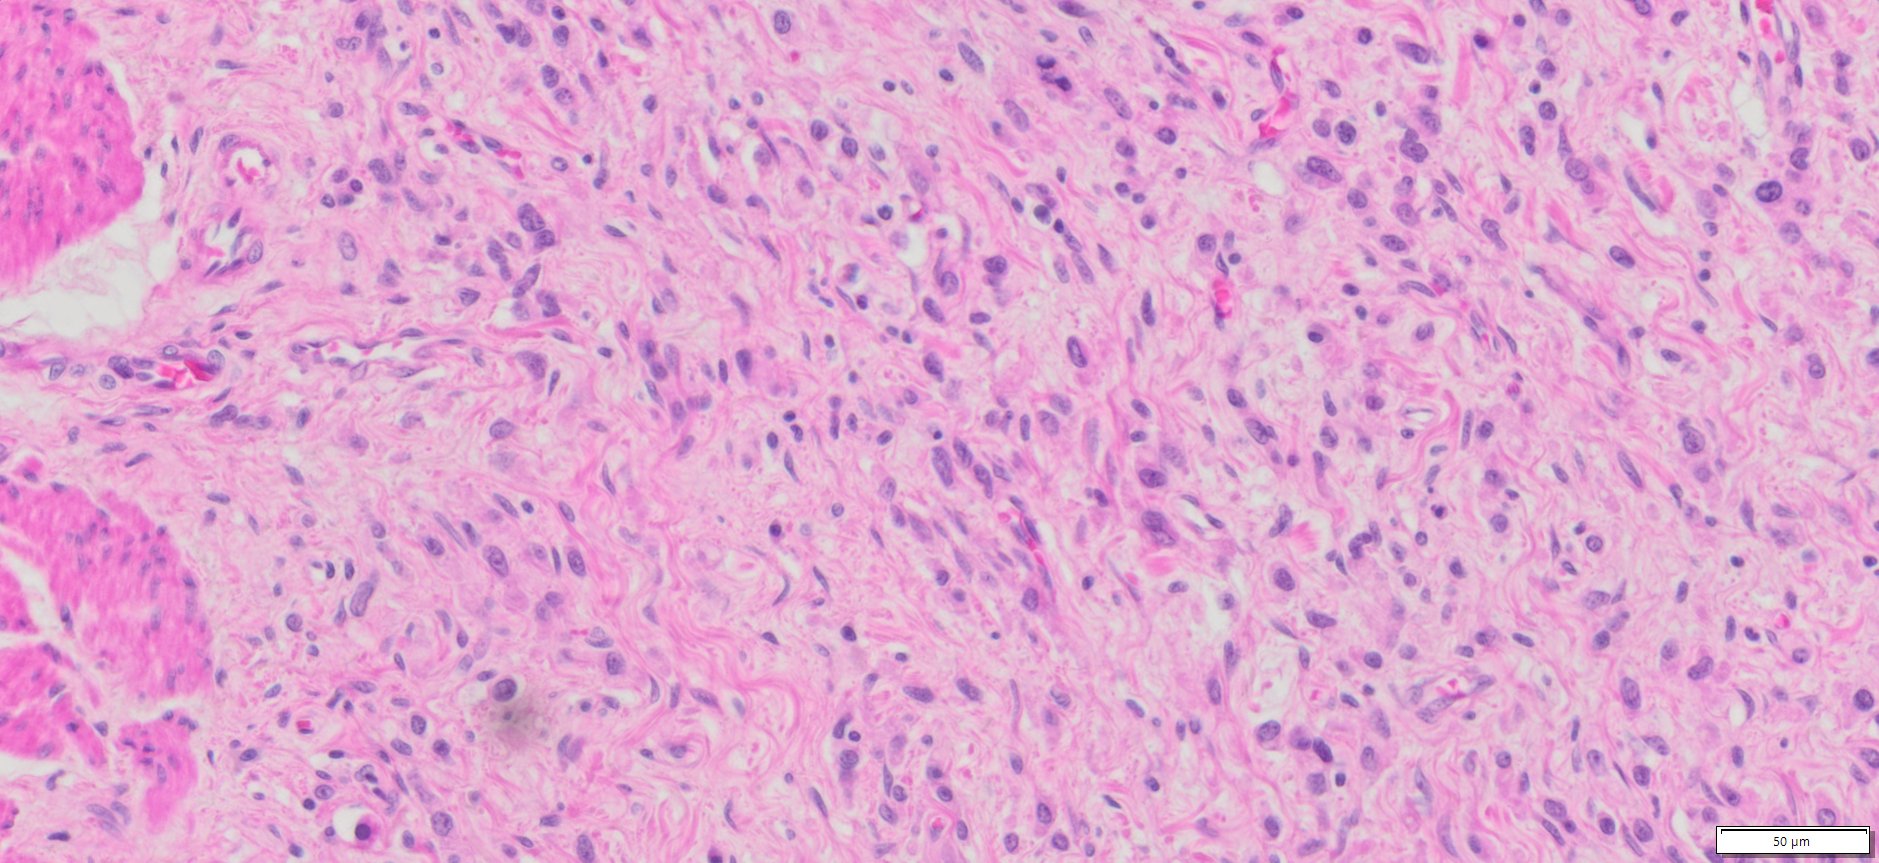

| Organ& Tissue | Pathology Diagnosis | Gender/Age | % Tumor Area | Grade | TMN Stage | Biomarkers |

| Human stomach | Poorly differentiated adenocarcinoma of the stomach | Male/52 | 10% | III | T3N3bMo |